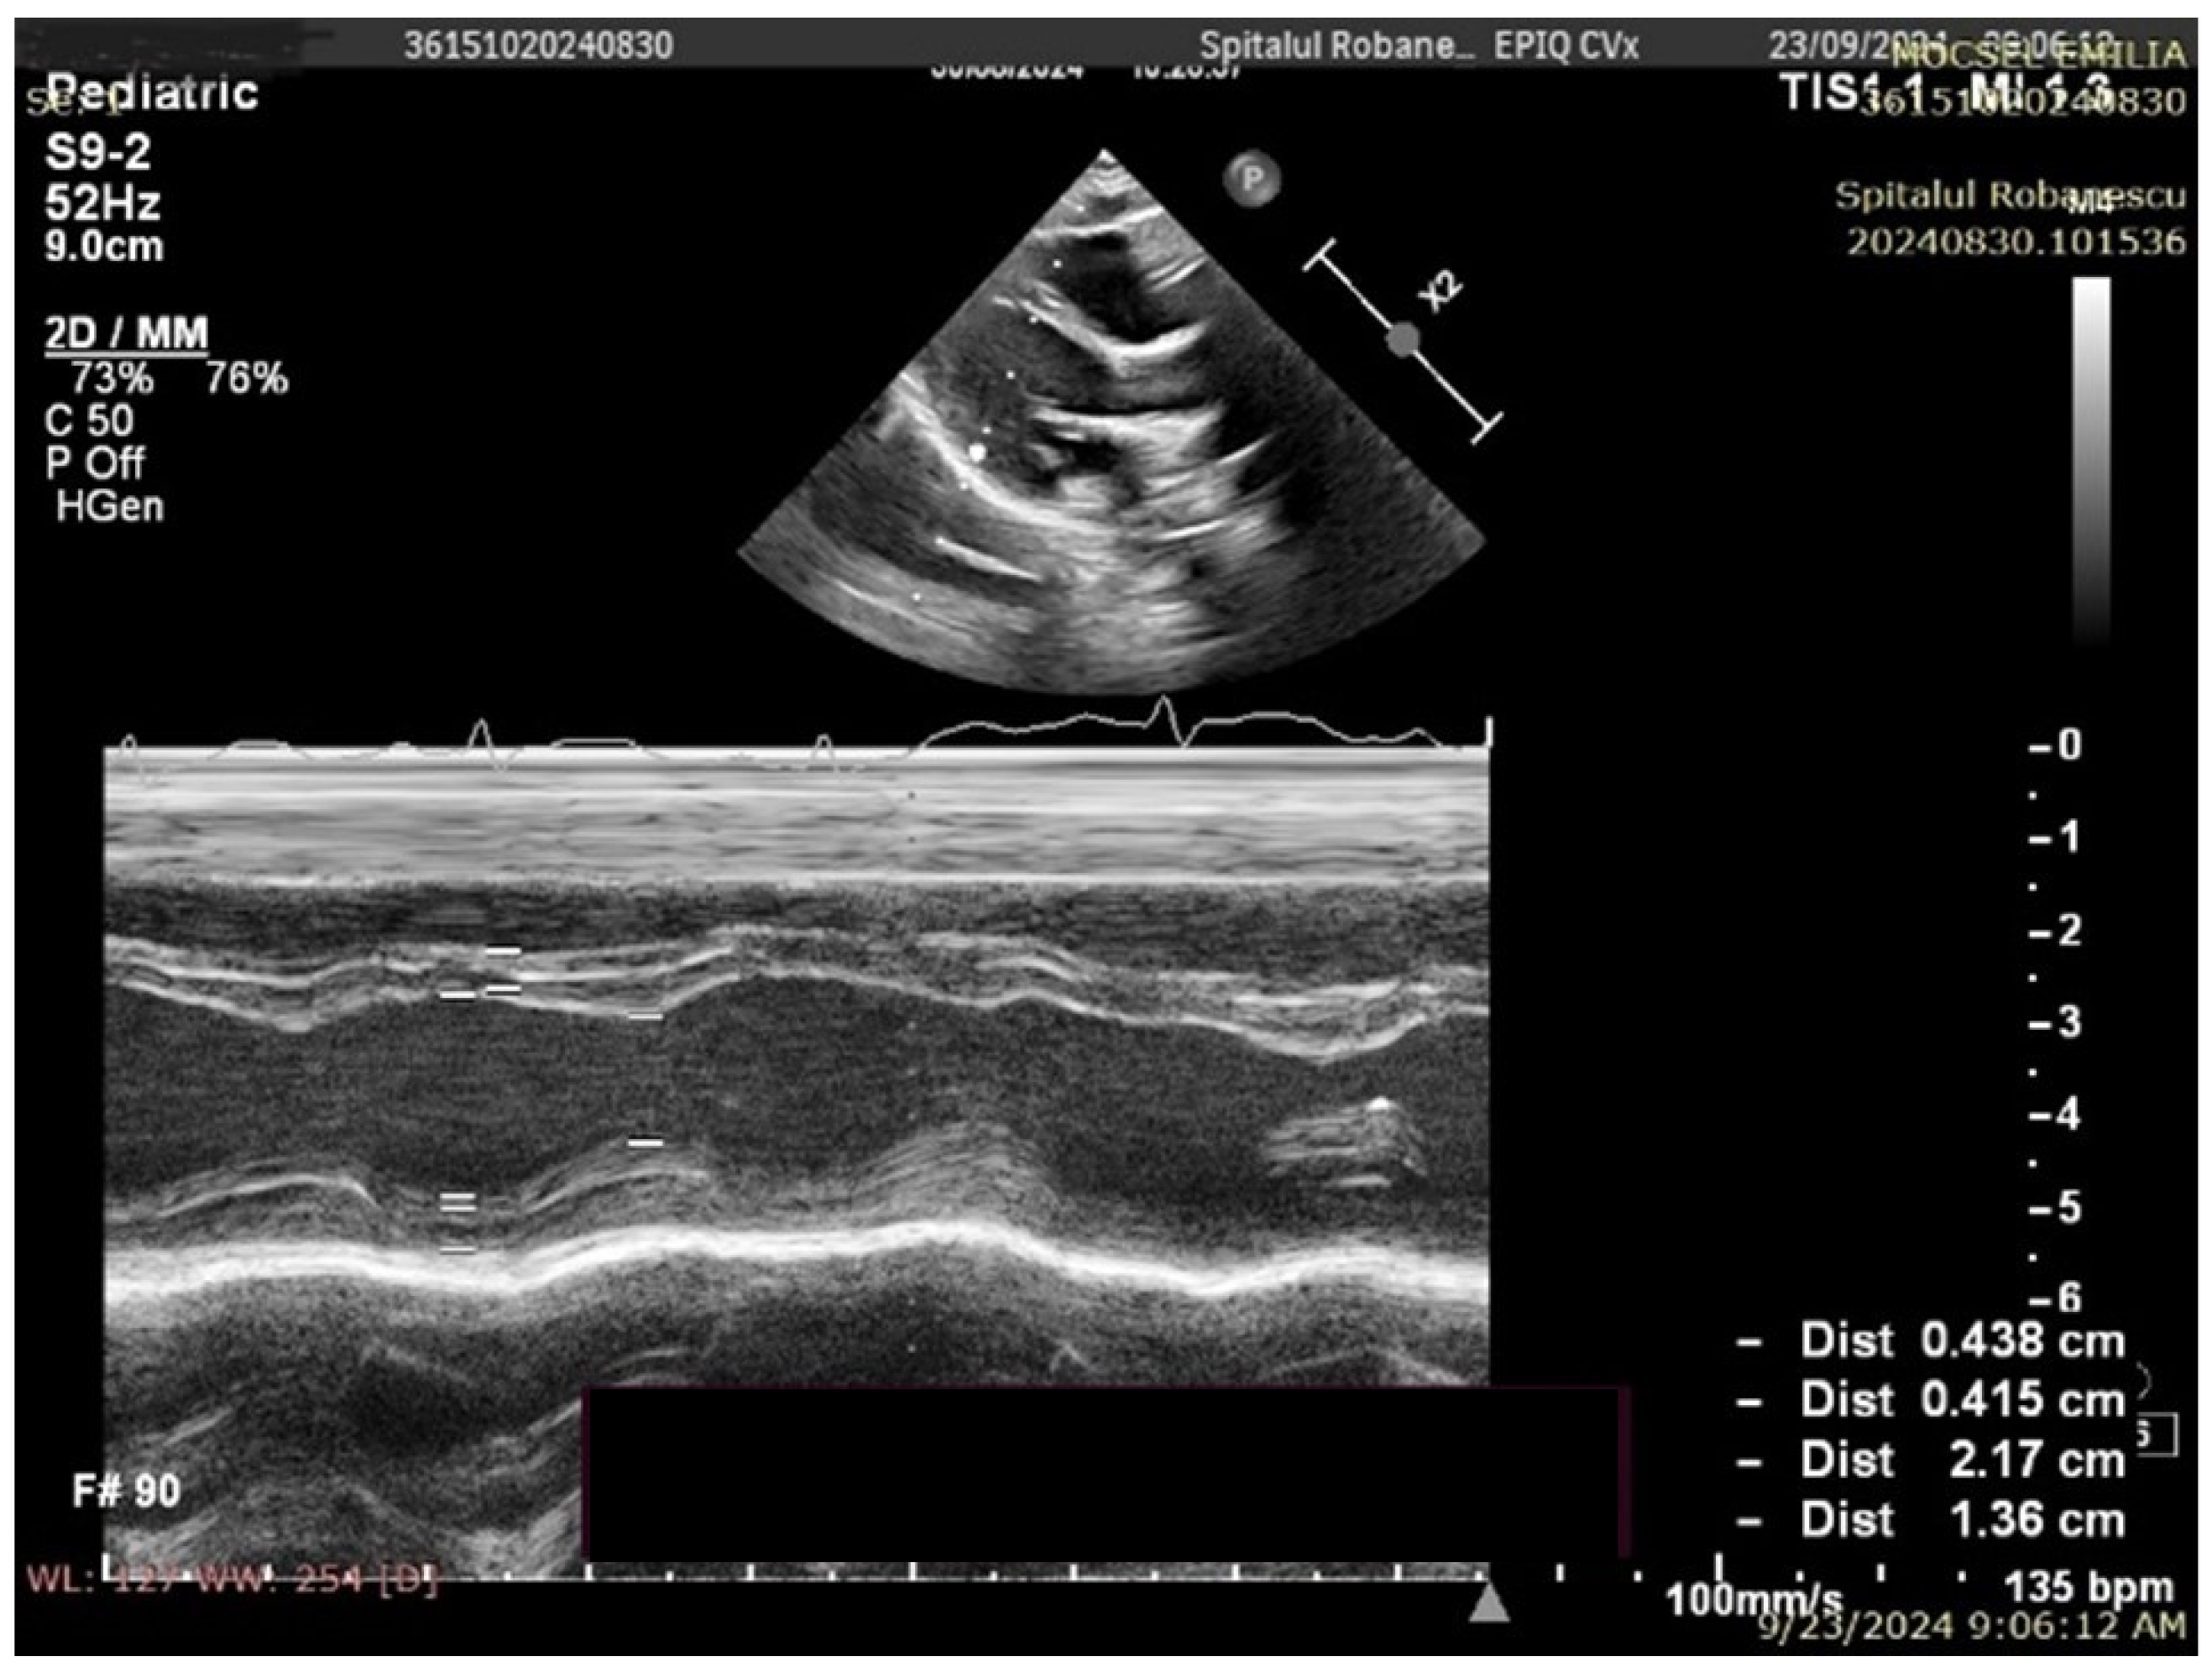

4.2. Echocardiographic Findings

| Cardiac ultrasound | |

| LVM (g) | 33.9 [21.44; 54.09] |

| LVM percentile | 6.49 [1.24; 19.49] |

| LVMI | 53 [46.36; 61.46] |

| Cardiac ultrasound | |||

| LVM (g) | 32.76 [19.45; 47.88] | 36.23 [25.26; 62.82] | 0.05 |

| LVM percentile | 1.98 [0.32; 9.94] | 13.57 [5.48; 25.08] | <0.01 |

| LVMI | 50.54 [43.04; 55.68] | 56.27 [47.46; 64.82] | <0.01 |